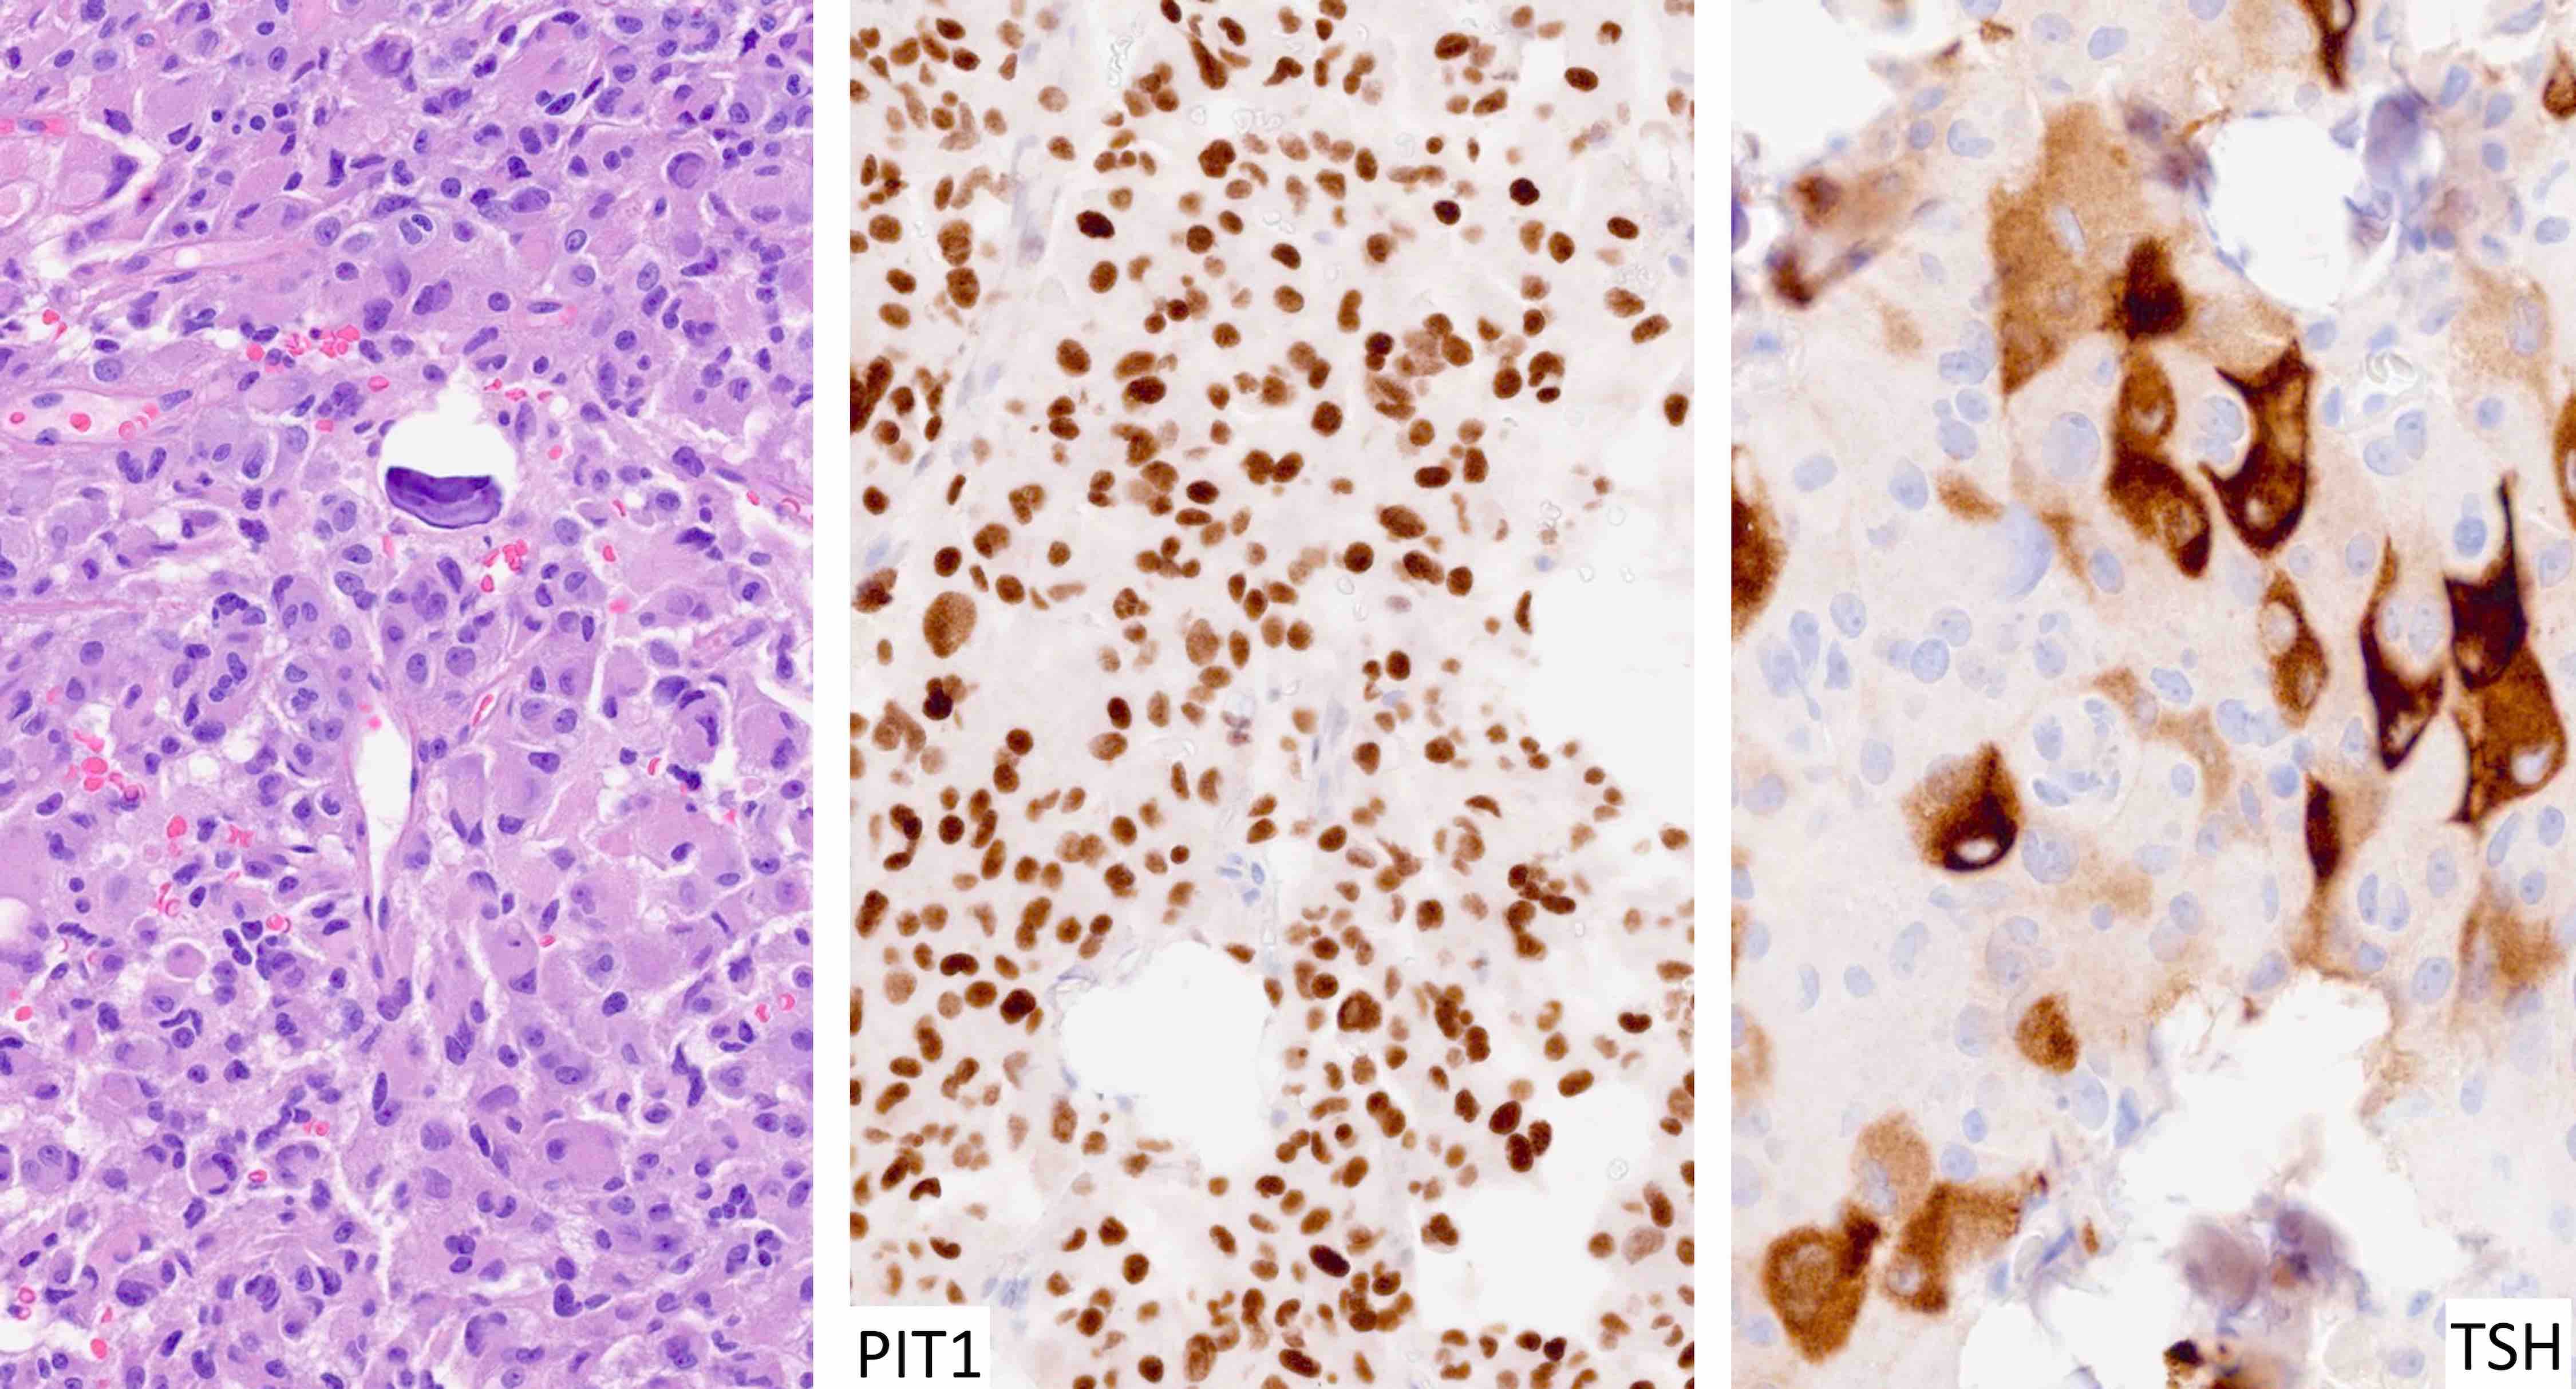

Contributed by Sylvia L. Asa, M.D., Ph.D.

| Thyrotroph tumor | Pit1, GATA3 | TSH | Variable keratins | Elevated TSH with or without hyperthyroidism |

- TSH secreting tumors cause increased TSH levels and are usually associated with elevated T3 and T4 levels, hyperthyroidism and goiter

- Stains for pituitary transcription factors (Pit1, Tpit, SF1, ER and GATA3) and hormones provide the basis for tumor classification (see Diagrams / tables)